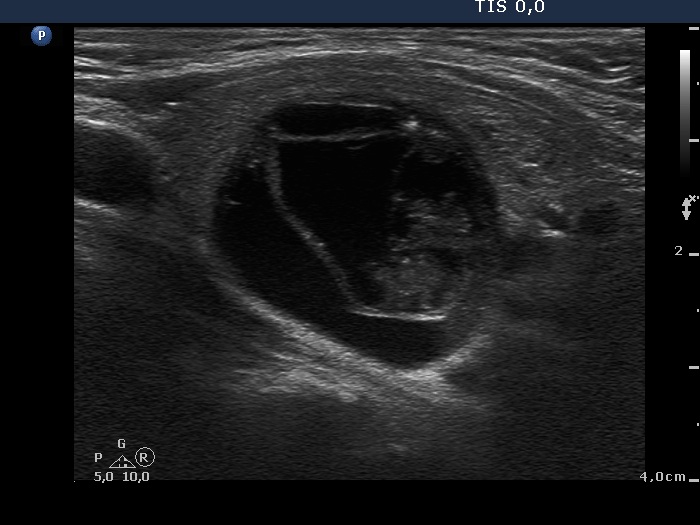

Ultrasonography. The thyroid was echonormal. There was moderately hypoechogenic nodule with blurred borders in the central part of the right lobe. A cystic nodule having echonormal solid part was found in the lower pole of the right lobe. The left lobe also has a cystic nodule.

Cytology of the moderately hypoechogenic nodule in the right lobe resulted in benign degenerative pattern. Two and 3 mL yellow fluid was removed from the cystic nodule in the right and left lobe, respectively. The cytology resulted in benign cystic degeneration in these cases.